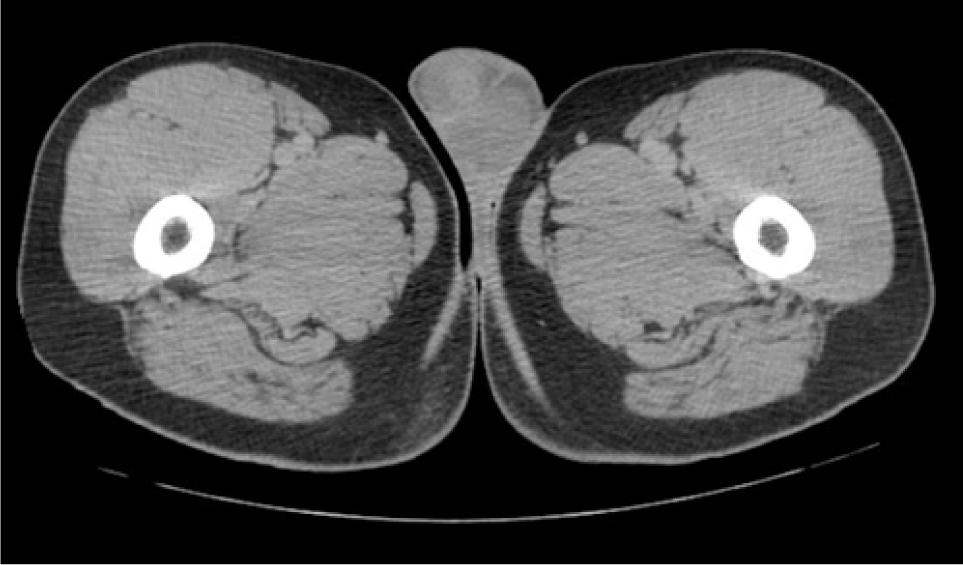

Core biopsy confirmed metastatic clear cell RCC in the paraspinal mass. The mediastinal and bilateral parenchymal masses were resected. Pathology for the mediastinal and left lung masses was positive for clear cell RCC, while hamartoma was confirmed in the right lobe. A PET/CT done 1 year later, showed suspicious uptake in the adrenal lesions being monitored. The right mass had a standardized uptake value (SUV) of 2.7, while the left mass had an SUV of 2.9. Labs showed normal levels of aldosterone, cortisol, plasma metanephrines, and normetanephrines. Biopsy of the right adrenal mass revealed pathology consistent with metastatic RCC. After an initial period of surveillance, the patient chose to proceed with systemic therapy and enrolled on a clinical trial. He had stable disease for 2 years when a CT urogram revealed a 1.7-cm enhancing right lower pole testicular mass (Figure 1). Physical examination revealed a palpable right lower pole testicular mass. Testicular cancer serum tumor markers were within normal limits. Ultrasound showed a 1.5 cm hypoechoic, hypervascular right lower pole mass (Figure 2). CT scans showed stability of prior metastatic lesions.

Figure 1: CT urogram showing 1.7-cm enhancing mass in the lower pole of right testicle.